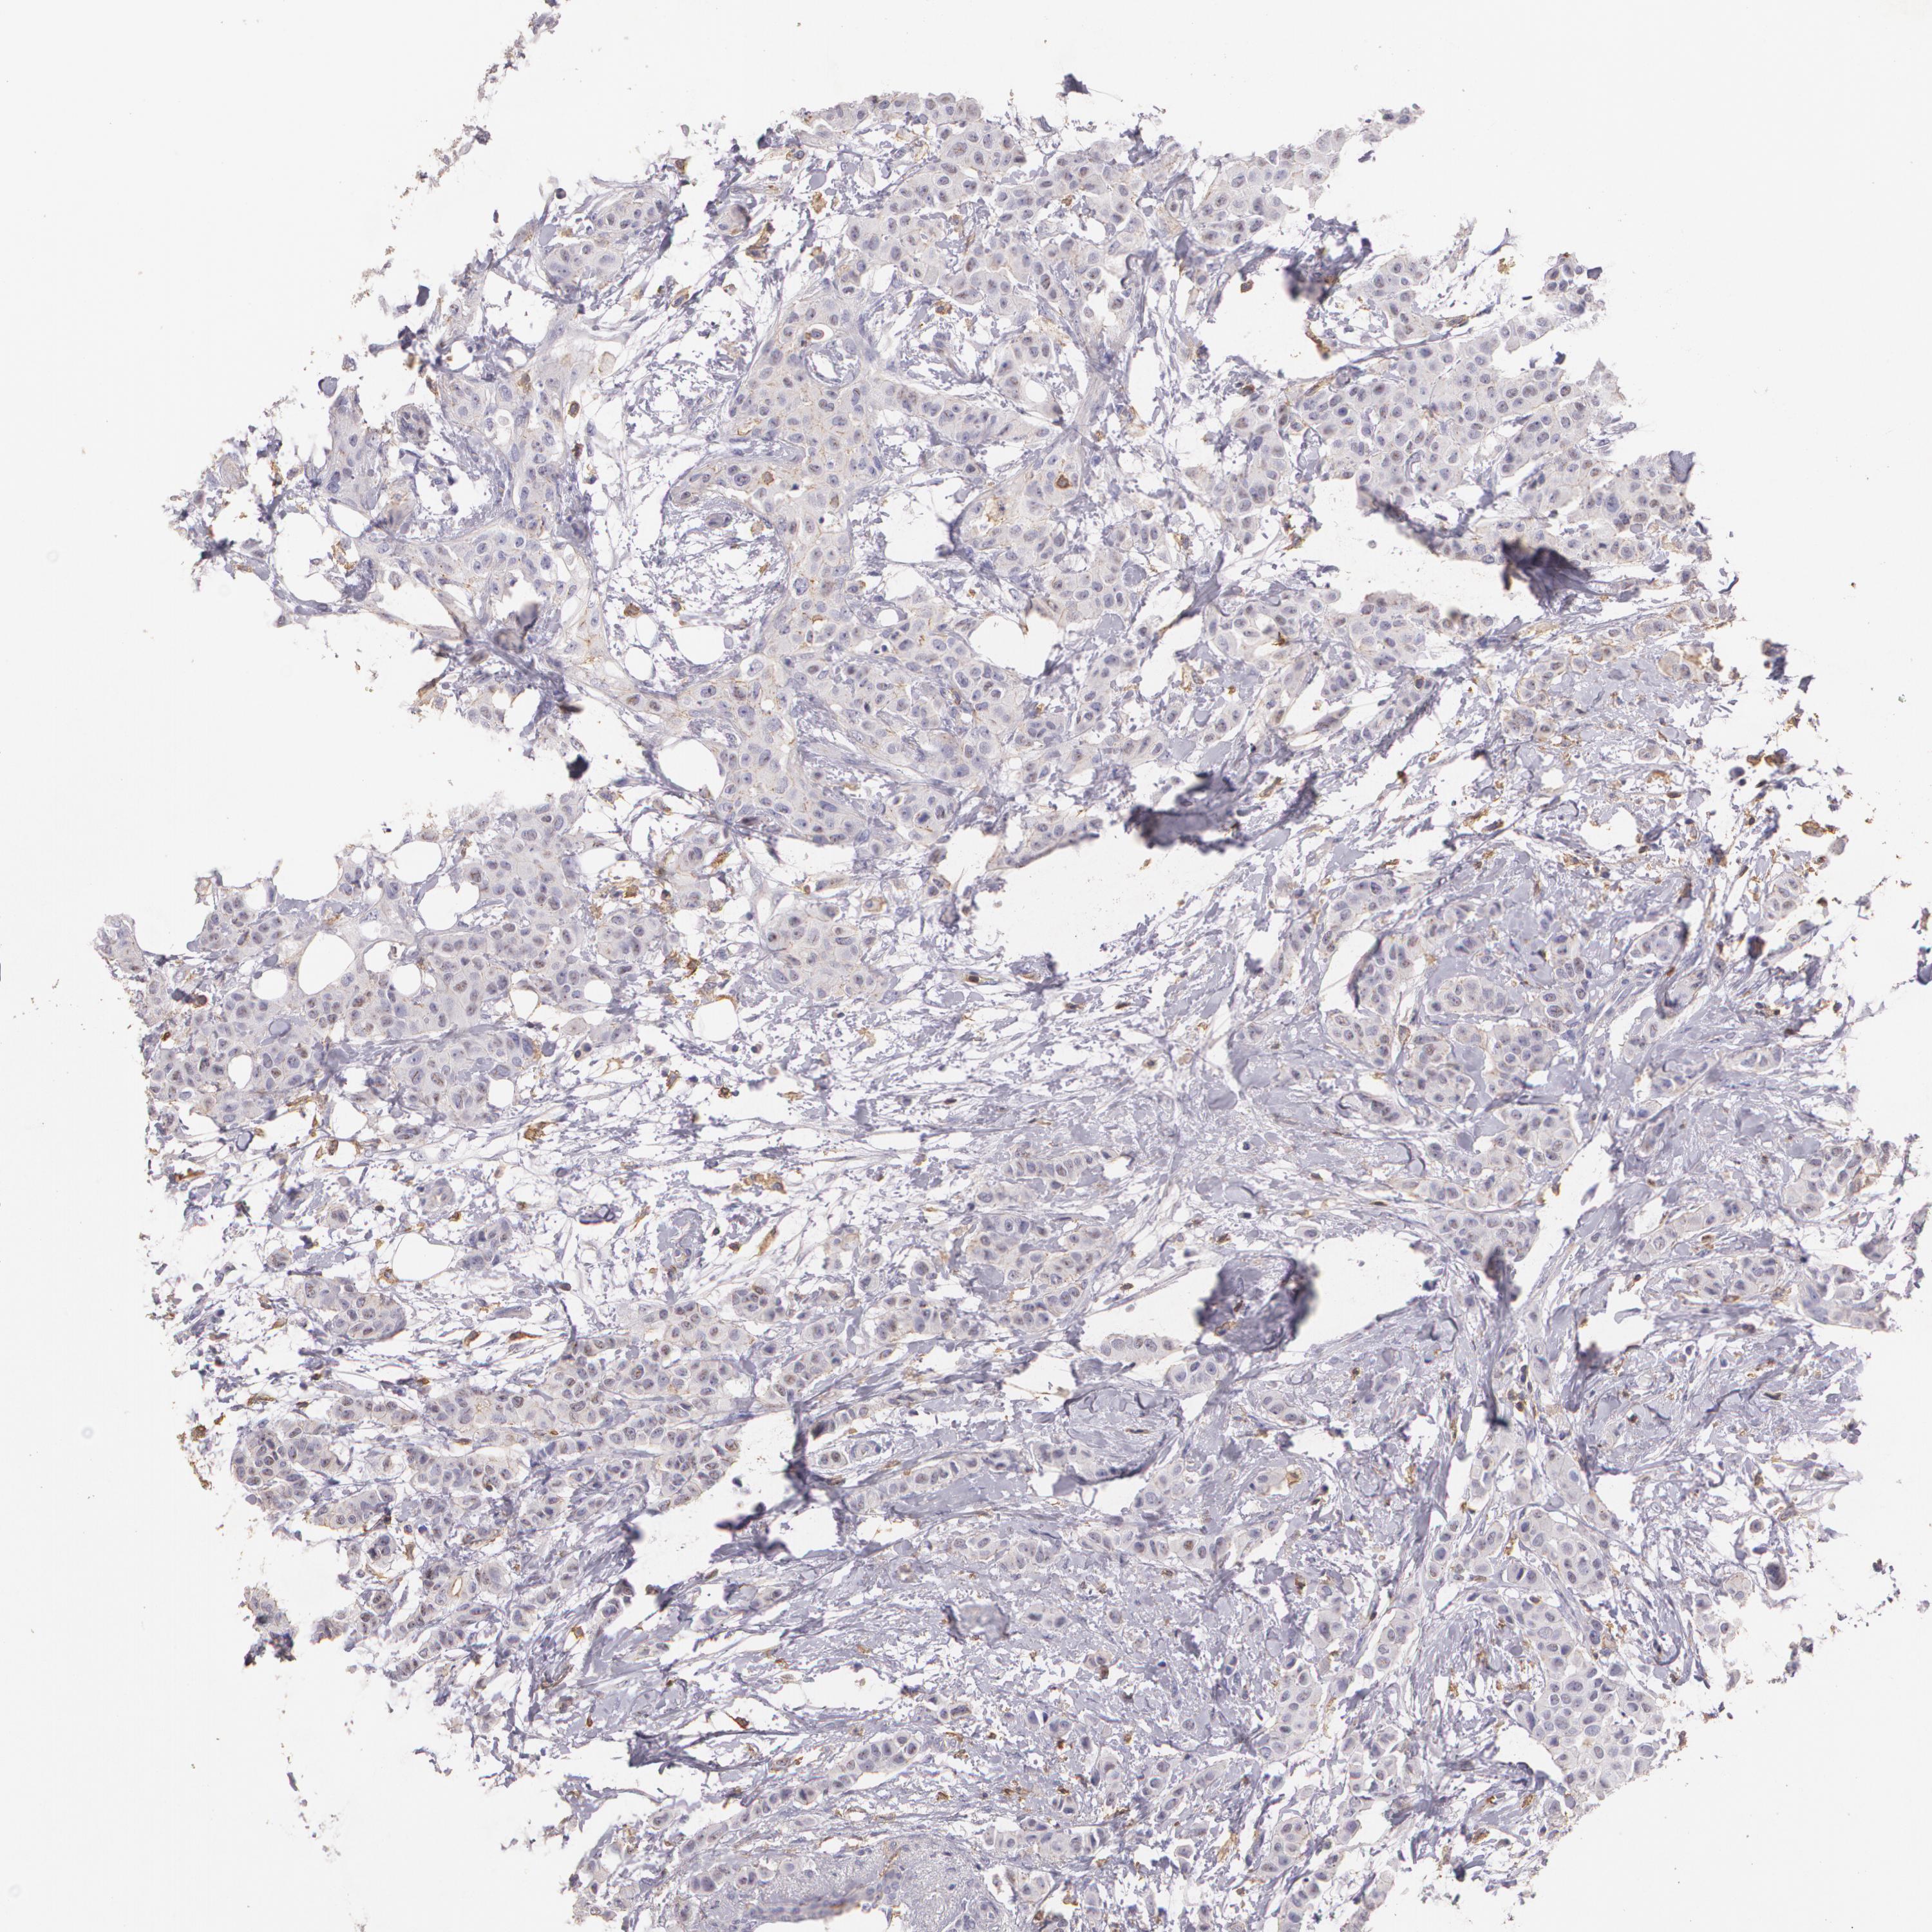

BRCA TCGA BRCA VALIDATION PROTEIN EXPRESSION

Breast cancer

Human cancer